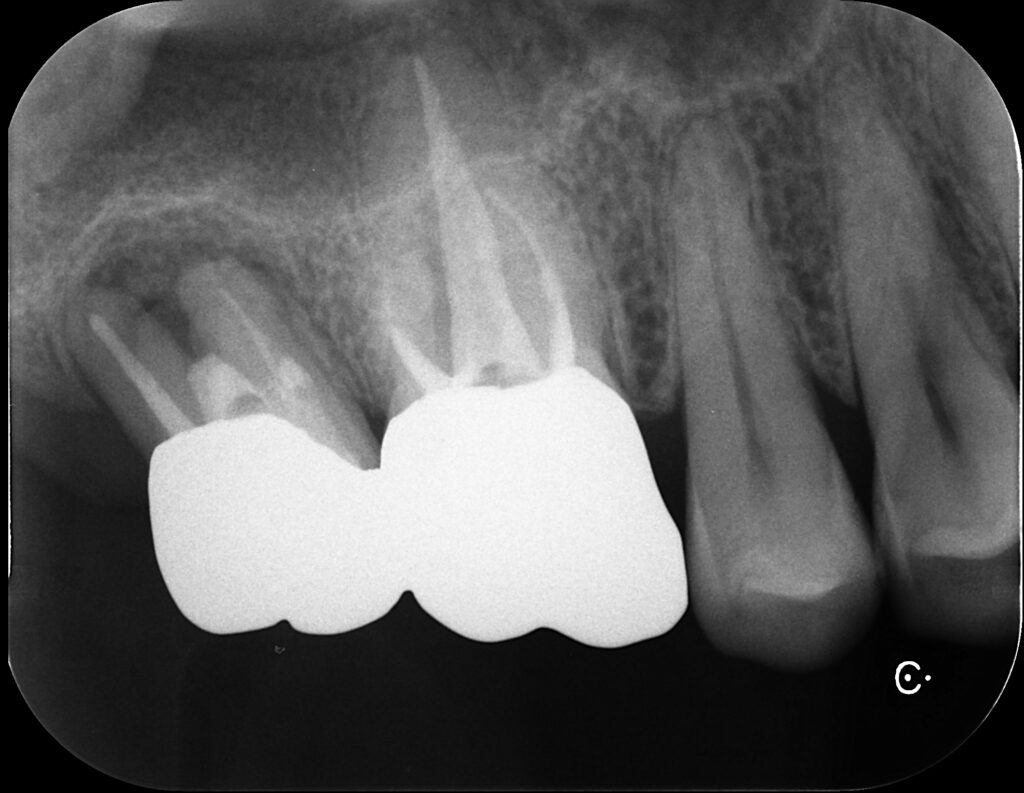

右側の写真は6番根管充填後。GP使用。

その後7番(一番左)も根充し、クラウンSET。

2年後

6年後

6年後はだいぶ根尖部にも骨ができてくれています。

7番の根分岐部(奥歯は根っこが複数あり、その股の部分)の

黒い部分は歯周病による骨の吸収なので仕方ありません。

ただし、痛みなどは全くなく噛めるそうです。